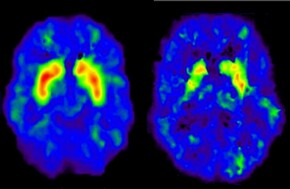

Wij maken de Google Maps van het lichamelijk weefsel

Wegens omstandigheden kan Zita Soons deze lezing niet geven. Zij wordt vervangen door Martijn Arts, PhD student Department of Surgery/ M4I Institutelees meer